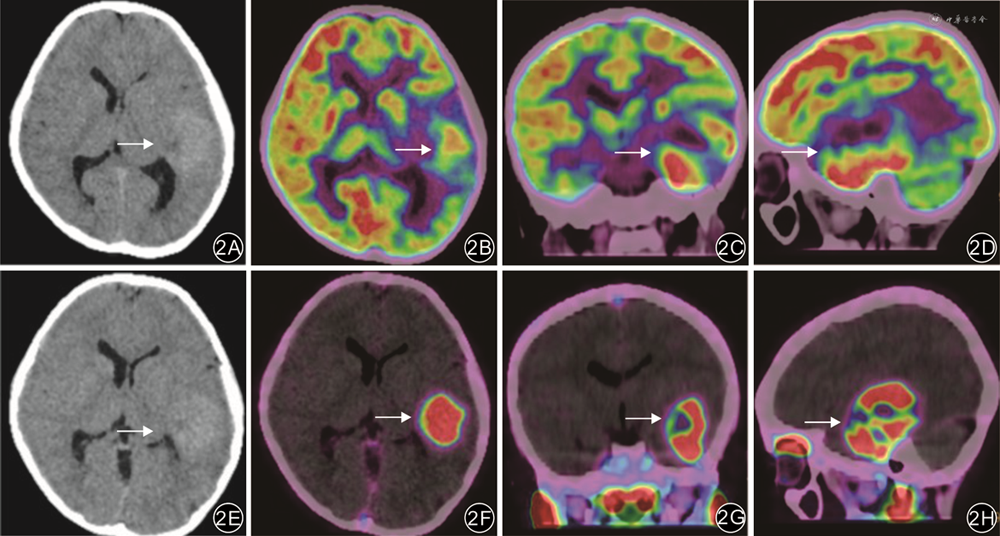

以正常脑灰质为对照,18F-PSMA-1007 PET/CT图像上HGG组和LGG组清晰显示病灶边界的病例数均高于18F-FDG PET/CT,差异均有统计学意义(P值均<0.05)。见表3。典型病例见图2。

由于脑胶质瘤的异质性和浸润性生长的特点,肿瘤边界的确定对于手术及术后放疗具有重要意义。由于正常脑实质缺乏对PSMA的生理性摄取,使图像对比度高,有利于大脑中代谢活跃病灶的显示。Şahin等[16]的研究结果显示,68Ga-PSMA PET/CT可清晰显示肿瘤界限,有助于区分肿瘤病灶和坏死组织,对精准指导勾画脑胶质瘤边界具有重要作用。Schwenck等[17]研究发现,与FDG PET/CT相比,PSMA进行PET/CT显像时肿瘤边界更为清晰。本研究结果也显示,HGG和LGG中18F-PSMA-1007 PET/CT清晰显示病灶边界的病例数高于18F-FDG PET/CT,与既往研究结论一致。本研究结果提示,18F-PSMA-1007 PET/CT在描绘肿瘤边界方面具有潜在优越性,可为患者手术及术后放疗提供精准影像学信息。